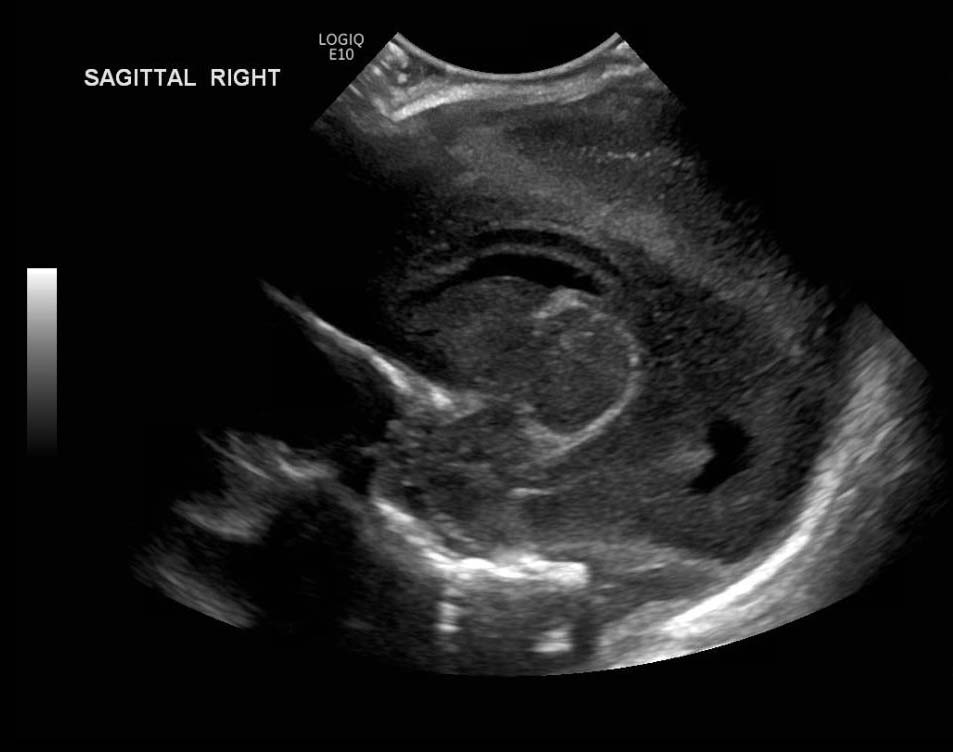

Indication: Evaluate for germinal matrix hemorrhage

Grade 2 germinal matrix hemorrhage

Sample ReportLeft germinal matrix hemorrhage involving the caudothalamic groove and layering in the occipital horn of the left lateral ventricle without hydrocephalus (grade 2).

No abnormal brain parenchymal echogenicity or extra-axial collections.

Premature sulcation pattern.